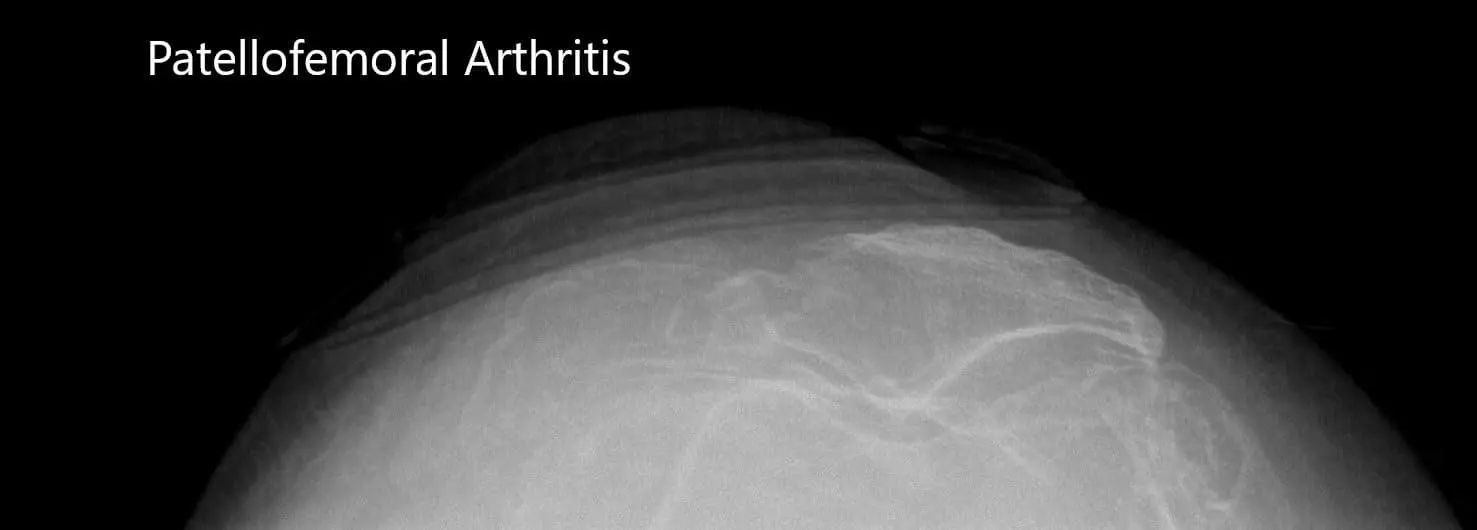

Preoperative merchant views of the bilateral patella showing severe osteoarthritis of the patellofemoral compartment.